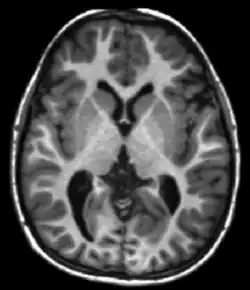

Neuroimaging

MRI diffusion tensor imaging of white matter tracts

MRI is the investigative tool of choice for neurological cancers over CT, as it offers better visualization of the posterior cranial fossa, containing the brainstem and the cerebellum. The contrast provided between grey and white matter makes MRI the best choice for many conditions of the central nervous system, including demyelinating diseases, dementia, cerebrovascular disease, infectious diseases, Alzheimer's disease and epilepsy.[22][23][24] Since many images are taken milliseconds apart, it shows how the brain responds to different stimuli, enabling researchers to study both the functional and structural brain abnormalities in psychological disorders.[25] MRI also is used in guided stereotactic surgery and radiosurgery for treatment of intracranial tumors, arteriovenous malformations, and other surgically treatable conditions using a device known as the N-localizer.[26][27][28] New Artificial intelligence in healthcare tools have demonstrated higher image quality and morphometric analysis in neuroimaging with the application of a denoising system.[29]